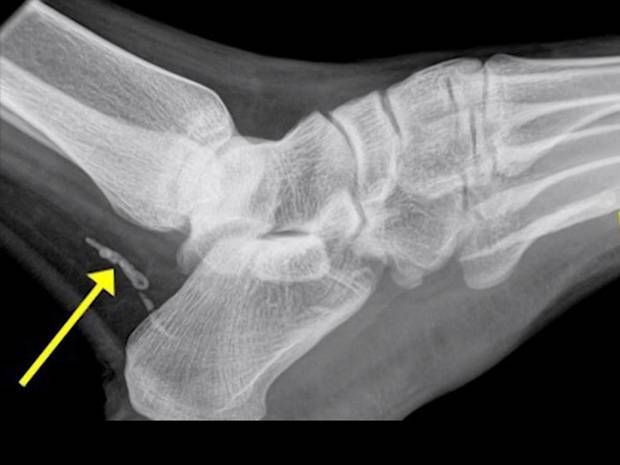

En lugar de una infección, el hombre en realidad tenía un parásito conocido como “gusano de Guinea”. Esto puede pasar debido al agua potable infectada. Probablemente, el gusano había estado viviendo dentro de él desde antes de partir hacia Australia. En esta radiografía se puede ver que el gusano está en dos partes. De alguna manera, murió en el cuerpo del hombre, y estaba empezando descomponerse.

Así se puede observar en las radiografías al gusano dentro de su cuerpo: